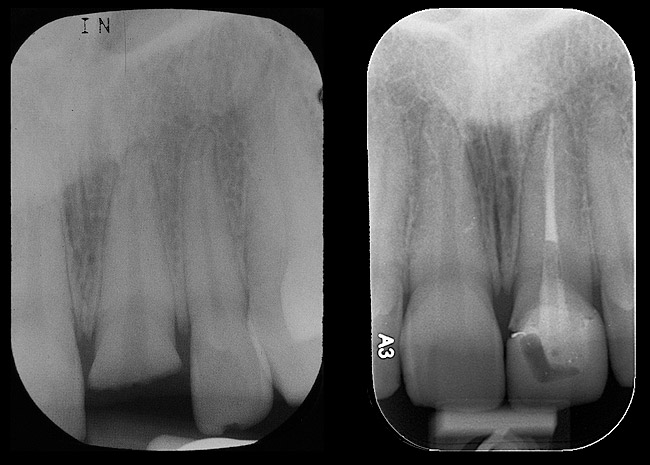

Figure 9: Implants supporting zirconia abutments and crowns, site Nos. 24 through 26—periapical view.

Figure 9

Figure 20  Screw-retained zirconia crown, customized zirconia stock abutment (one-piece restoration), site No. 9—final periapical view.

Figure 20

After the zirconia abutments were torqued to 20 Ncm, cotton and composite were used to cover the screw access openings. Figure 7 and Figure 8 show the finished feldspathic porcelain crowns on implants in sites Nos. 24 through 26, and on teeth Nos. 22, 23, 27, and 28; all crowns were cemented with dual-cure resin cement. Good remodeling of gingival architecture is also apparent in Figure 7. As predicted, the free gingival margin (FGM) on No. 23 is approximately 2 mm coronal to those of the adjacent implant crowns on Nos. 24 through 26 (Figure 7); as per the patient’s initial statement, this discrepancy was not an esthetic concern to her. Figure 9 shows the final post-restoration periapical view.

Emergency endodontic treatment had been completed to manage the traumatically exposed root canal; Figure 10 shows the pre-treatment (Ellis Class III crown fracture) and post–endodontic-treatment periapical views of tooth No. 9. The restorative dentist temporarily cemented a glass-reinforced fiber post and used a fiber-reinforced composite core buildup material as an immediate provisional. Several weeks later, a provisional bis-acryl temporary crown on No. 9 was cemented on a larger-diameter glass-reinforced fiber post retaining a new fiber-reinforced composite core. Figure 11 shows the final feldspathic porcelain crown placed by the restorative dentist. During the fabrication and cementation of this crown, the remaining root appeared intact and the tooth was asymptomatic.